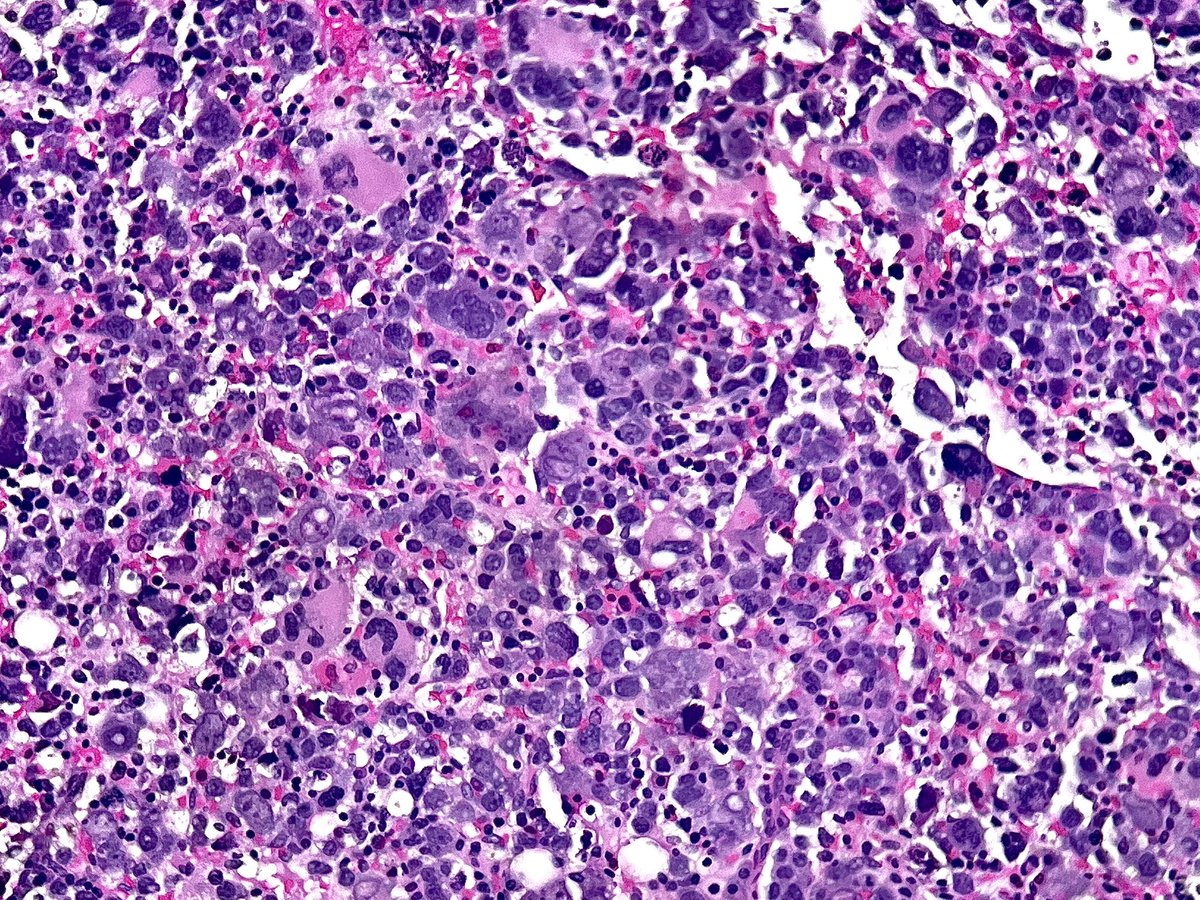

#Pathresidents: Let’s take a look at two biopsy cores (from the same patient) and decide what to call them.

Take a look at both cases (“A” in this post, “B” in reply). Cast your vote. Then, read on for some teaching points geared towards trainees and general fans of #GUPath.